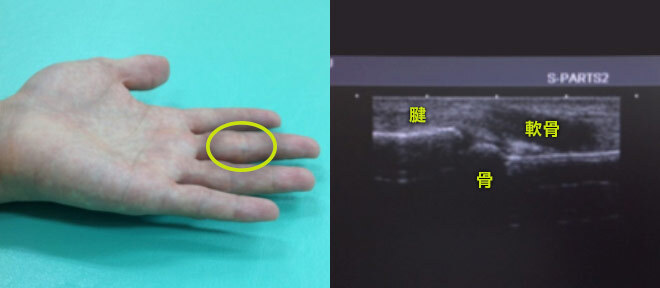

いわゆる“エコー検査”のことで音の反射と各組織の音の浸透速度の違いを利用し骨はもちろんレントゲンでは見られない筋肉・靭帯・軟骨などの軟部組織をリアルタイムで観察することができる装置です。

従来のエコーは周波数が低く体表に近く浅い領域、筋肉・靭帯・腱などでは画像が不鮮明であったが近年プローブの高周波数化や画像のデジタル化に伴い体表領域でも鮮明な画像が観察できるようになりました。

エックス線検査に異常がなくても靱帯断裂、軟骨損傷などが伴えば意外に治療は長引くものです。

当院では超音波画像(エコー)により以前は見逃していたかもしれない軟部組織観察の精度向上に努めています。

これらの損傷では治療の際、損傷部位と状態を明確に把握することが大事です。

内部の状態を視覚的に観ることで治療の精度が上がります。また繰り返し経過を観察することで仕事や運動の復帰時期を計ることにも役立ちます。